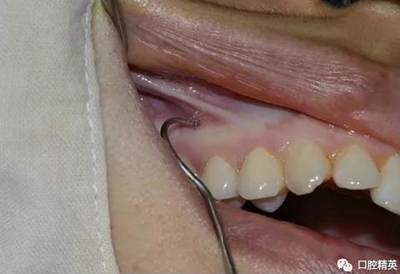

先使用刀背劃一垂直于頜骨矢狀平面的印記,以確定種植釘?shù)慕h(yuǎn)中位置。

常用11號(hào)尖刀片劃一個(gè)小切口,切開粘骨膜,牙科小挖匙分離粘骨膜。

再次,植入微型種植體,在附著牙齦處不需要粘骨膜翻瓣,在牙槽黏膜處則需要切開黏膜以避免植入時(shí)軟組織被卷入,植入部位通常在膜齦結(jié)合部位或偏根方2~3mm,植入角度與骨面垂直并傾斜15~20度,即向根尖方向植入,術(shù)后拍根尖片以確認(rèn)與牙根的關(guān)系。術(shù)后口服抗生素預(yù)防感染并進(jìn)行口腔衛(wèi)生宣教。